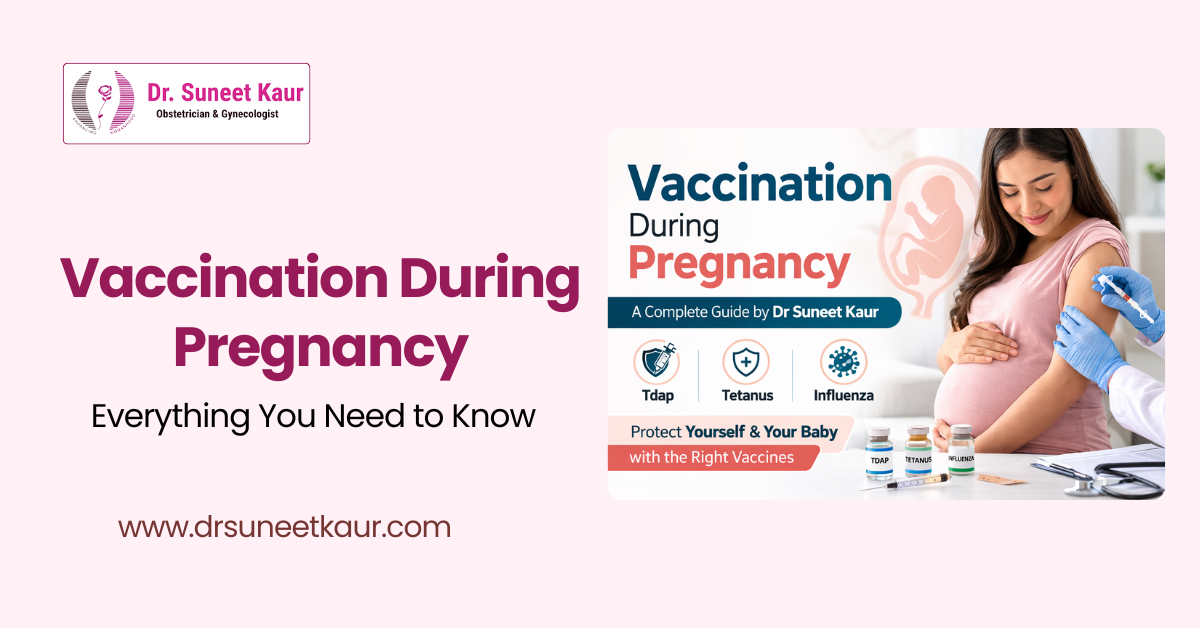

- Cervical Cancer Vaccination

Our Blogs

Comprehensive Care for Every Stage of a Woman’s Health

Advanced and compassionate care in Obstetrics, Gynecology, Infertility, and Robotic Surgery – all under one expert you can trust.